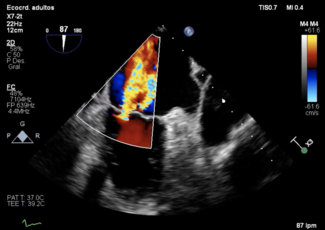

Clinical Images

Mireia Martínez, MD; Paula Vela, MD; Juan Casanova-Sandoval, MD, PhD; Kristian Rivera, MD

A 42-year-old man was admitted with an inferior ST-segment elevation myocardial infarction. Emergency coronary angiography revealed a critical lesion of the middle right coronary artery, which was treated with a 3.5 x 18-mm...